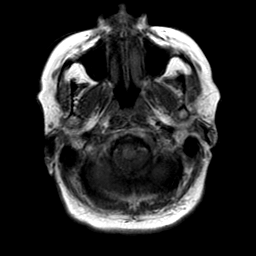

Cerebral hemorrhage, MR Study mr-t1 -- Slice #3

[Home][Help][Clinical] Slice 3